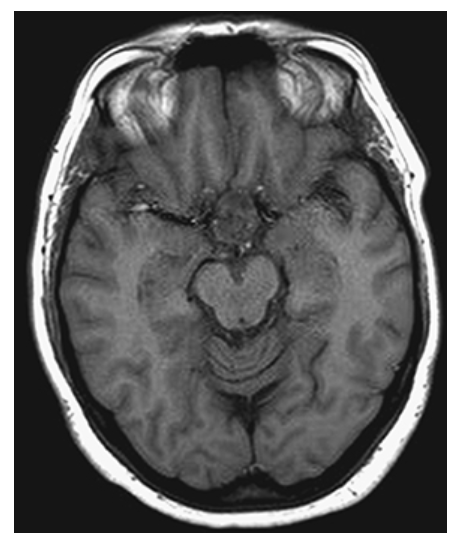

Brain Metastasis. Postcontrast T1W coronal MR shows multiple enhancing lesions with surrounding low-signal edema involving the gray-white junction, white matter, and cerebellum.